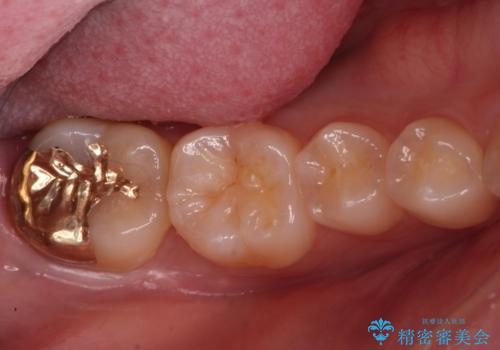

Dr. 岡田康成の症例写真

担当医 岡田康成<2025年10月31日更新>